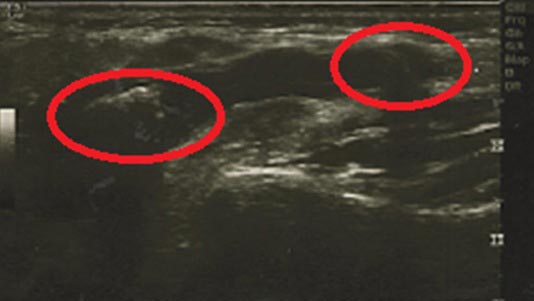

Результаты и их обсуждение. В результате применения сиалолитотрипсии фрагментация камней была достигнута у 36 из 39 пациентов (92,3%, р=0,0323). У 16 больных во время сиалолитотрипсии или сразу после 1-го сеанса произошла фрагментация конкремента, после 2-го сеанса — у 8 человек, после 3-го сеанса — у 6 пациентов, после 4-го — у 3, после 5-го — у 3 больных (рис. 2 и 3).

Рис. 2. Ультразвуковое исследование пациента с конкрементом в протоке околоушной слюнной железы до сеанса сиалолитотрипсии